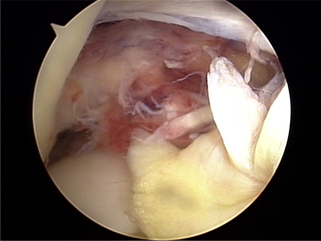

x-ray 사진

전방십자인대 재건후